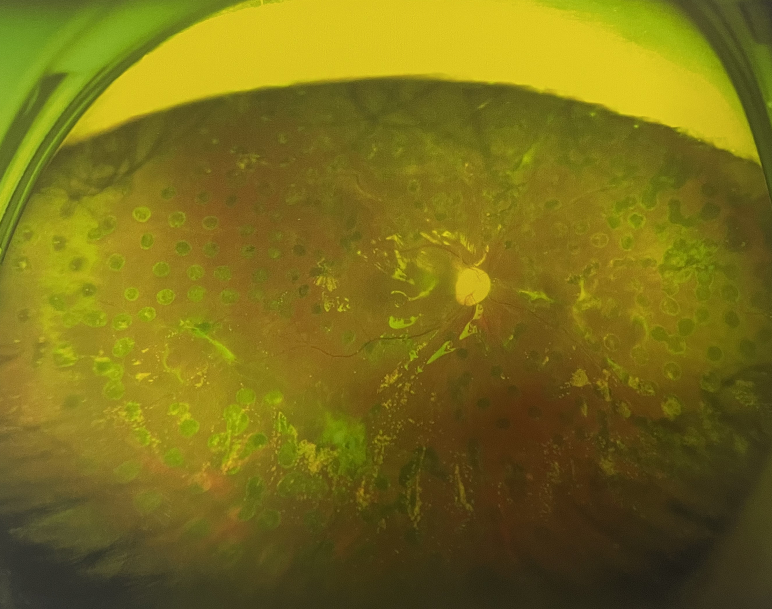

右眼術(shù)后

4個月后王女士來院取硅油,取油后視力恢復(fù)到0.6。“當(dāng)時來的時候真的只能看到模糊的影子,特別害怕覺得完了,想說眼睛估計(jì)要瞎了,沒想到手術(shù)后視力竟然提升了,現(xiàn)在也看得比較清楚了。”王女士說到。

張小虎醫(yī)生表示,糖網(wǎng)病進(jìn)展到嚴(yán)重增殖期帶來的視力損傷往往是極其嚴(yán)重的,目前王女士右眼從術(shù)前0.02恢復(fù)到術(shù)后0.6,已屬十分難得。